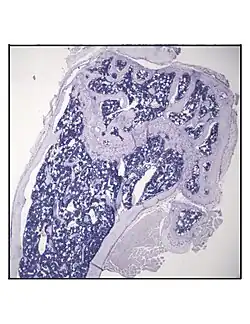

In order to understand the physiology of BMAT, various analytic methods have been applied. BMAds are difficult to isolate and quantify because they are interspersed with bony and hematopoietic elements. Until recently, qualitative measurements of BMAT have relied on bone histology,[51][52] which is subject to site selection bias and cannot adequately quantify the volume of fat in the marrow. Nevertheless, histological techniques and fixation make possible visualization of BMAT, quantification of BMAd size, and BMAT's association with the surrounding endosteum, milieu of cells, and secreted factors.[53][54][55]

Representative distal femur histologic section of a 16-week-old C57BL/6 mouse after 6 weeks of calorie restriction demonstrating an increased quantity of marrow adipocytes.